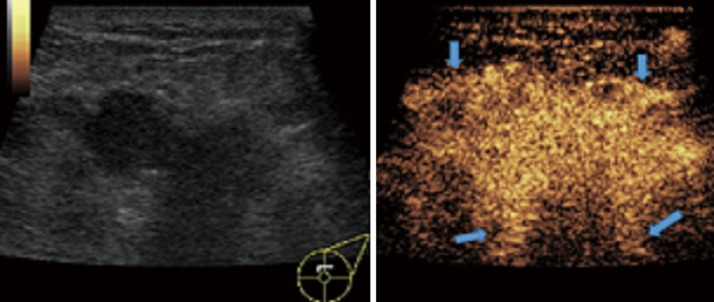

In this study, CEUS of LABC showed high enhancement, and its internal and peripheral blood vessels showed “solar sign” (Figure 1). Relevant studies showed (25) that angiogenic factors could stimulate the breast tissue to produce new blood vessels that extend into the tumor in malignant tumors. And then it would form a network of blood vessels that changed with the growth and necrosis of the tumor. Due to the anisotropy of malignant tumor growth, its internal vascular path was messy, twisted and variable. The characteristic of “solar sign” was often seen as an important indicator for the diagnosis of benign and malignant tumors (23,25). In this study, the tumors of invasive ductal carcinoma all presented as “fast in and slow out”. Analysis suggested that there might be abundant arterial regeneration in the tumor. They were rapidly enhanced. Related studies showed that malignant tumors were composed of abnormal blood vessels with increased tortuosity. It tended to increase flow resistance. At the same time, hypoxia and acidosis decreased red blood cell fluidity. They could also lead to venous insufficiency, poor reflux, and thrombosis, which leaded to form a slow withdrawal (27-29). Some study revealed that breast cancer presented as “fast in and fast out”. It might be because of the formation of arteriovenous fistula inside the tumor. However, Wan et al. [2012] (25) showed that the enhancement mode could also be “fast in and slow out” in benign tumors. It might be related to the blood supply characteristics of the breast tumor. So the mode of enhancement cannot be used as a distinguishing feature of benign and malignant breast tumors. In addition, in this study, 11 lesions (11/40, 27.5%) had no, equal or low enhancement areas, including 5 lesions (5/40, 12.5%) had no continuous enhancement areas. In 3 of the 5 lesions, the internal cystic area was found in conventional ultrasound, but the area of no enhancement in CEUS was significantly larger than that in conventional ultrasound. In 2 lesions, no cystic area was found in conventional ultrasound, but CEUS showed non-liquefaction necrosis area without enhancement (Figure 2). In addition, for non-mass breast cancer, it was difficult to be presented in conventional ultrasound. CEUS could show relatively clear boundaries. In particular, CEUS could clearly show the area of lesions and internal vascular conditions, assisting in diagnosis and guiding the area of puncture biopsy (Figures 3,4). Therefore, CEUS was more likely to detect muscle or skin infiltration than conventional ultrasound, providing a reference for accurate clinical T staging of LABC.

Figure 1.

One case of locally advanced invasive ductal carcinoma with CEUS “solar sign”. Female, 42 years old, left breast had mass for 1 month. This was a double contrast image of CEUS. The lesion presented high enhancement, and the area of lesion was significantly larger than that of conventional ultrasound. The boundary was not clear, and the blood vessels showed “solar sign”. CEUS, contrast-enhanced ultrasonography.